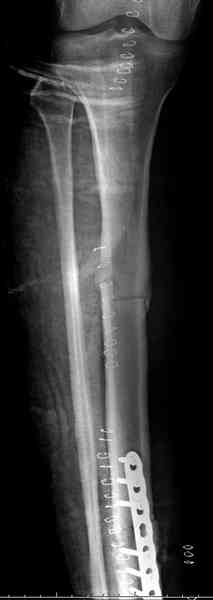

Не оригинальное, подход не раз был демонстрирован нас в стране проф. Анатолием Федоровичем Лазаревым (ЦИТО), который это называет "металлокаркасная пластика". У нас в институте в другом отделении он

помогал сделать несколько таких металлокаркасов, только, насколько я помню, без блокируемых стержней. А в мире эта методика довольно давно

применяется, хотя и не массово. Например, осенью прошлого года на конференции общества Кюнчера в Страсбурге было хорошее сообщение на эту тему. 17 больных, результаты уже до 5 лет.

Да хорошие, все нормально при наблюдении до 5 лет. У всех все состоятельно.

КАН> Что происходит с металлической сеткой на отдаленном сроке, заполняется ли

КАН> она костным веществом, а может этого вовсе и не требуется, были ли

КАН> изломы имплантов?

У некоторых обрастает. Надо ли этого добиваться - вопрос открытый. У одного, кажется, больного потребовалась ранняя ревизия из-за погрешностей при операции, сильно несоосно засинтезировали.

Как минимум эндопротез трубчатой кости. Несущий часть нагрузки.